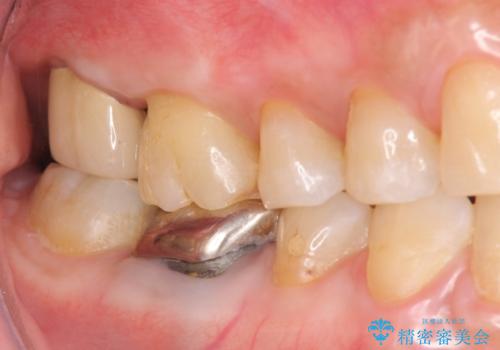

歯髄方向 歯肉方向へと深い 2種類の大きな虫歯

#17は失活歯で歯肉方向への縁下カリエス、#16は生活歯であるものの歯髄ギリギリの処置となるであろうとが予想される治療です。

歯周外科、マイクロスコープを用いた虫歯治療を行い歯を残す治療計画を立てます。